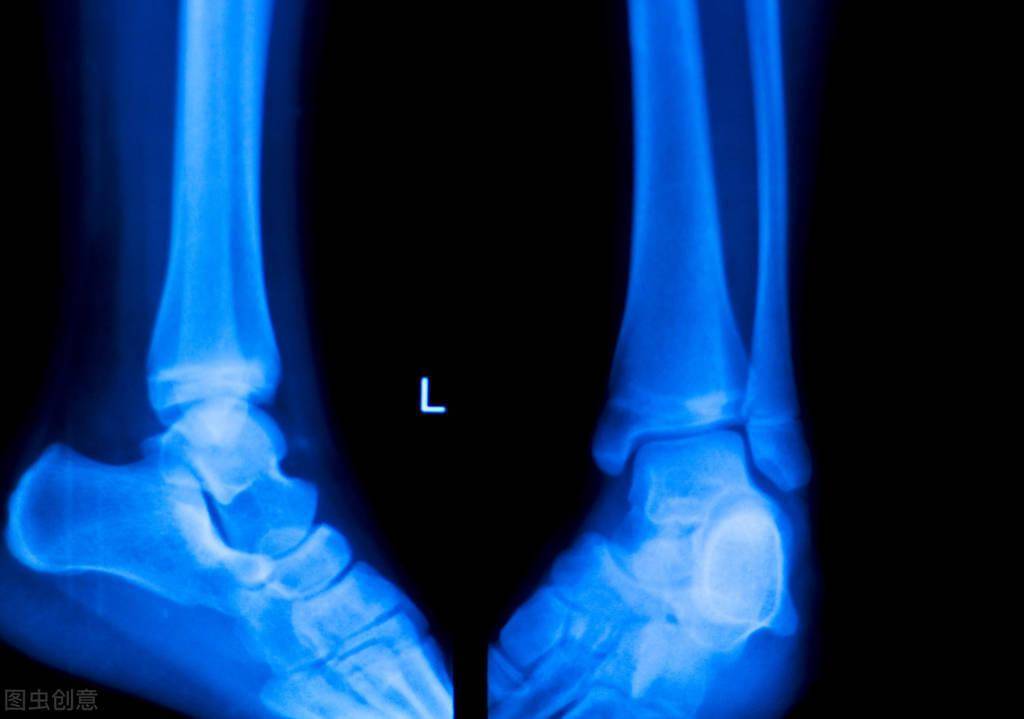

足跟骨刺x光片

足跟骨刺x光片,足跟骨刺图片

足跟骨骨折

踝关节x光片